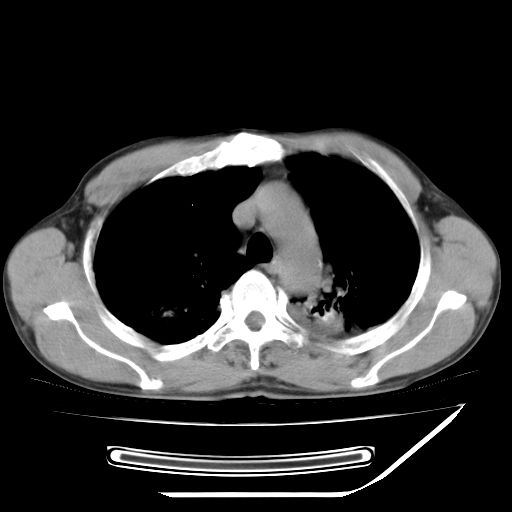

男,59岁,“结核性胸膜炎”30余年,胸部经常疼痛,多次x检查提示“肺部”炎症。腹部疼痛5日,b超提示:“肝内短管结石,余显示不清,建议进一步检查。”

两肺结核并右侧胸腔积液;脾脏、腹腔及腹膜后淋巴结结核[陈旧性];肝内胆管结石

胸部腹部都是结核(双肺。纵隔淋巴结,肝脏,脾脏,肠系膜)

两肺结核并右侧胸腔积液;脾脏、腹腔及腹膜后淋巴结结核[陈旧性];肝内胆管结石。直肠息肉?

结核,是血行播散还是淋巴?

一元论——结核。